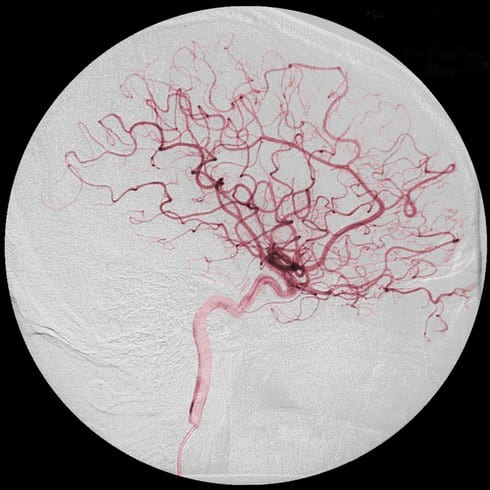

Удаление купероза лазером – одна из самых эффективных процедур, выполняется без наркоза. Расширенные капилляры исчезают на глазах, при этом на коже не остается рубцов. Стенки поврежденного сосуда спаиваются, он перестает функционировать и со временем удаляется организмом.

Используют для процедуры лазерный луч, работающий в диапазоне зеленого и желтого спектра. Эти лучи, прежде всего воздействуют на сосуды кожи, а не на клетки эпидермиса.

Как удалить купероз лазером

лечение купероза на лице лазером

Чаще всего используется неодимовый лазер, он самый эффективный.

Использование лазера

На данный момент лазер является наиболее эффективным методом борьбы с капиллярной сеточкой на лице. Отзывы в интернете говорят о высокой эффективности процедуры. Цена на процедуру довольно высокая, но она оправдана быстрый действием. Она безболезненная и достаточно щадящая для кожи.

Лечение купероза фотовспышками

Лечение купероза фотовспышками, или лазером – это единственный метод на сегодняшний день, позволяющий быстро решить проблему сосудистых образований любой степени выраженности. Лазерные лучи, проходя сквозь кожу, целенаправленно воздействуют на поврежденные капилляры, нагревая их и приводя к естественной электрокоагуляции, запаиванию сосуда. Поступление крови прекращается, и он обесцвечивается.